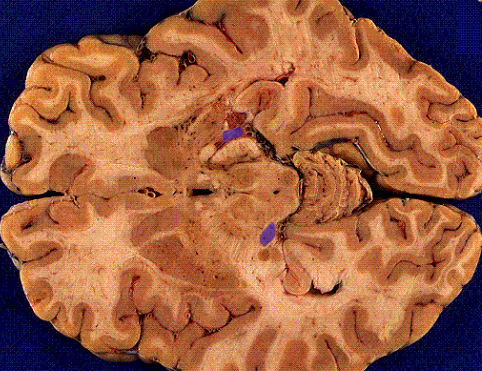

calcarine sulcus

light yellow

primary visual cortex

Pink area

Primary Visual cortex (V1, area 17)